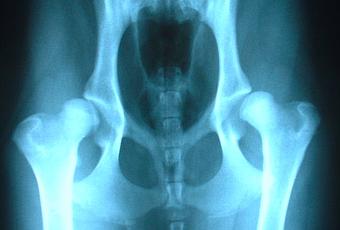

La cadera consiste en una articulación que se mantiene unida por una cápsula articular, tendones y ligamentos. La cabeza (parte superior) del hueso del muslo o del fémur forma la bola que entra en el zócalo o acetábulo, que es parte de la pelvis. Esta articulación de la cadera se ajusta de tal manera que la bola gira libremente en su zócalo. La cabeza del fémur está cubierta por un cartílago liso que hace que la articulación de la cadera se deslice fácilmente durante el movimiento de la articulación.

El borde del zócalo también está revestido de cartílago, que forma el labrum y sella y estabiliza la articulación.

Una persona que tiene displasia de cadera puede tener una articulación de cadera que es la forma equivocada, o una toma de cadera que no cubre completamente la cabeza femoral. Esto provoca un desgaste anormal de los cartílagos en la articulación, lo que lleva a una dislocación de la articulación. Una articulación de la cadera displásica es poco profunda o fuera de lugar y se desgastará más rápido que una articulación normal.

Para confirmar el diagnóstico, pueden utilizarse rayos X y otras técnicas de imagen como la RM .